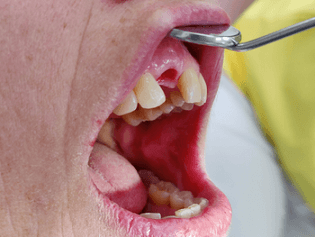

In diesem Fall hätte eine Brückenversorgung in regio 11 viel gesunde Zahnhartsubstanz gekostet. Daher fiel die Entscheidung der Patientin auf eine Implantatkrone. Neben des wiederholten Bruchs der Interimsprothese aufgrund des Tiefbisses stellte die provisorische Versorgung aufgrund der Lage im Frontzahnbereich hohe Anforderungen. Die Patientin verfügt überdies über eine hohe Lachlinie, bei der die Gingiva komplett sichtbar ist. Um den ästhetischen Ansprüchen gerecht zu werden, war eine gründliche Planung und längerer Vorlauf erforderlich. Das Ziel war nicht nur, ein ästhetisch befriedigendes Ergebnis zu liefern, sondern dieses auch langfristig zu erhalten. Deswegen dauerte die Vorbehandlung mit Socket Preservation, PA-Behandlung, Augmentation, Implantation und Gingivaformung durch die provisorische Krone insgesamt neun Monate.